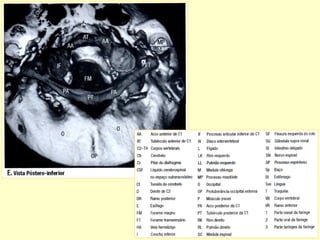

Conteúdos intra-raquianos

RELAÇÕES ANATÔMICAS DA COLUNA

Avaliaçao intra

Raquiana

MIELOGRAFIA (DESUSO)

LESÕES INTRAMEDULARES

LESÃO INTRADURAL EXTRAMEDULAR

LESÃO EXTRADURAL INTRARAQUIANA

LESÃO EXTRA RAQUIANA